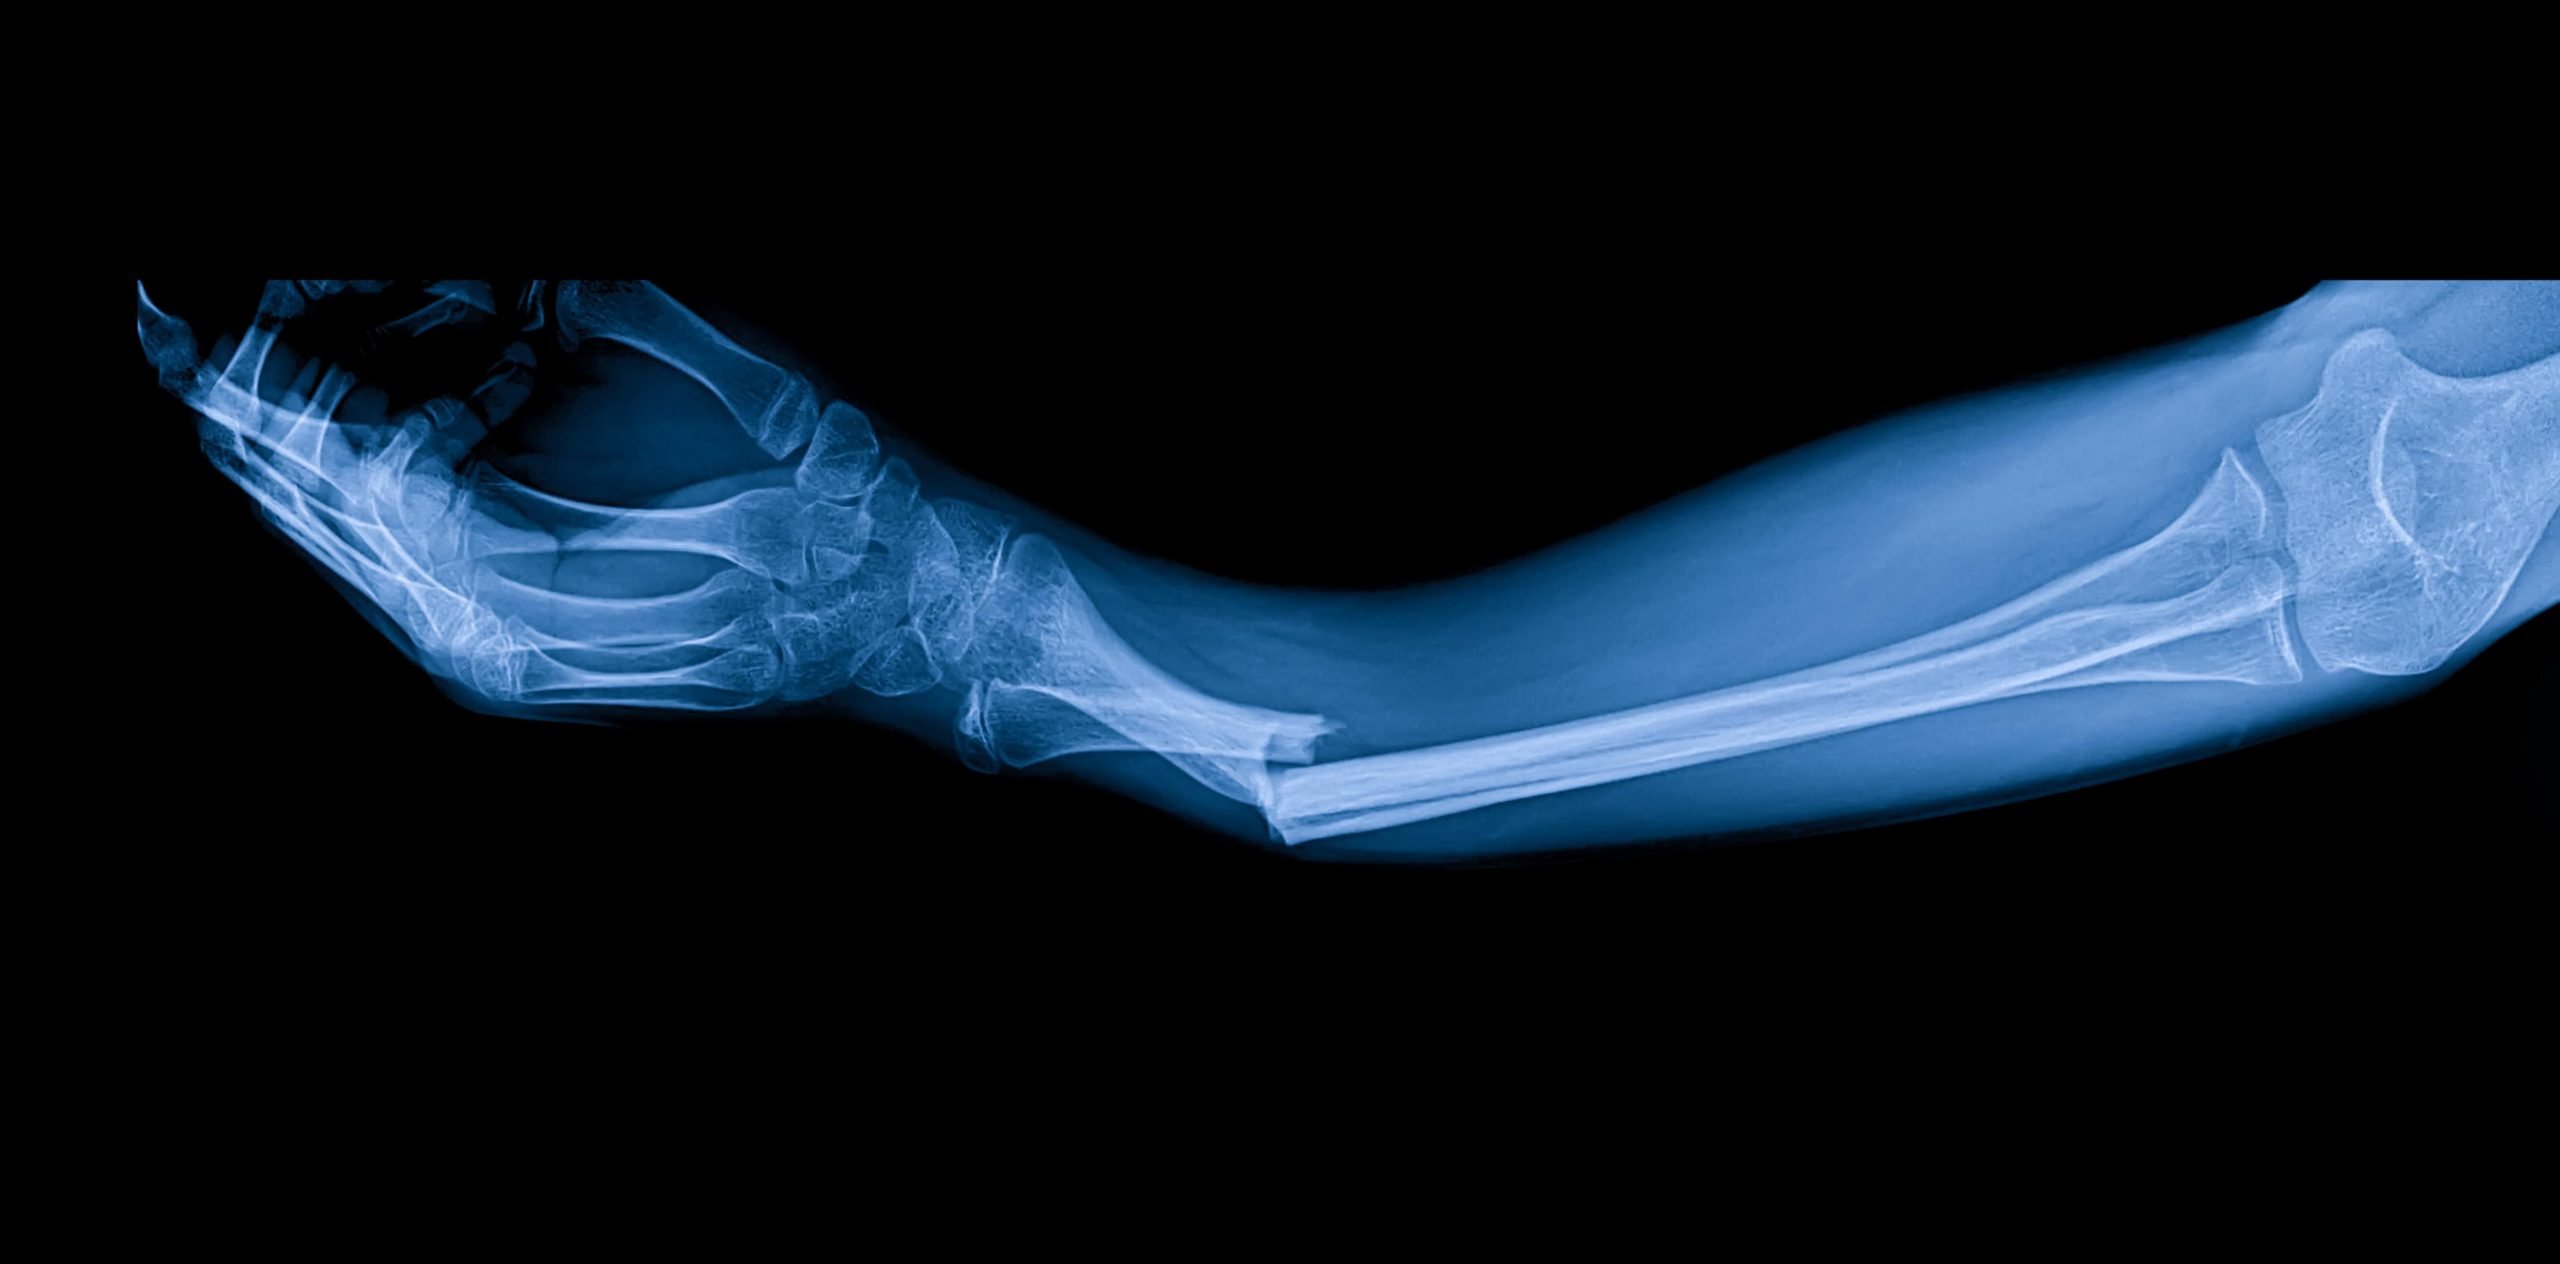

Биологический материал, вдохновленный устрицами, может изменить ортопедическую хирургию.

Китайские исследователи создали уникальный медицинский клей, способный соединять сломанные кости в считанные минуты.